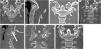

Material and methodsThis case series included patients over 15 years of age who were presented with acute or subacute atlantoaxial instability at C1-C2 due to fractures of the odontoid process, C1 vertebra, or C2 vertebral body. Surgical details and fusion criteria were described. Due to the absence of comparison groups, only descriptive statistical methods were employed.

ResultsA total of 11 patients (8 men, 3 women; mean age 41.5 ± 18.2 years) underwent fully percutaneous transarticular C1-C2 fixation. The mean operative time was 115.0 ± 30.8 min for patients stabilized using a Halo device and 80.6 ± 33.2 min for those immobilized with a Mayfield clamp. The mean blood loss across all cases was 38.8 ± 8.7 mL. One patient died from concurrent cardiac pathology. Two patients were lost to follow-up due to relocation, leaving 8 patients for final assessment. At final follow-up, the mean VAS score was 2 ± 1.5 and the mean NDI score was 5.3 ± 5.2. All patients with preoperative neurological deficits improved by one level on the ASIA scale. Fusion was achieved in 7 of 8 cases (87.5%), and 1 patient (12.5%) developed a stable C1-C2 pseudoarthrosis.

ConclusionOur initial clinical experience demonstrated that fully percutaneous posterior transarticular C1-C2 stand-alone screw fixation using cannulated instruments could be a feasible and safe procedure. Critical requirements for this technique include complete reduction of atlantoaxial dislocation, compression in the lateral joint region, adequate intraoperative visualization, and strict adherence to specific screw trajectories.